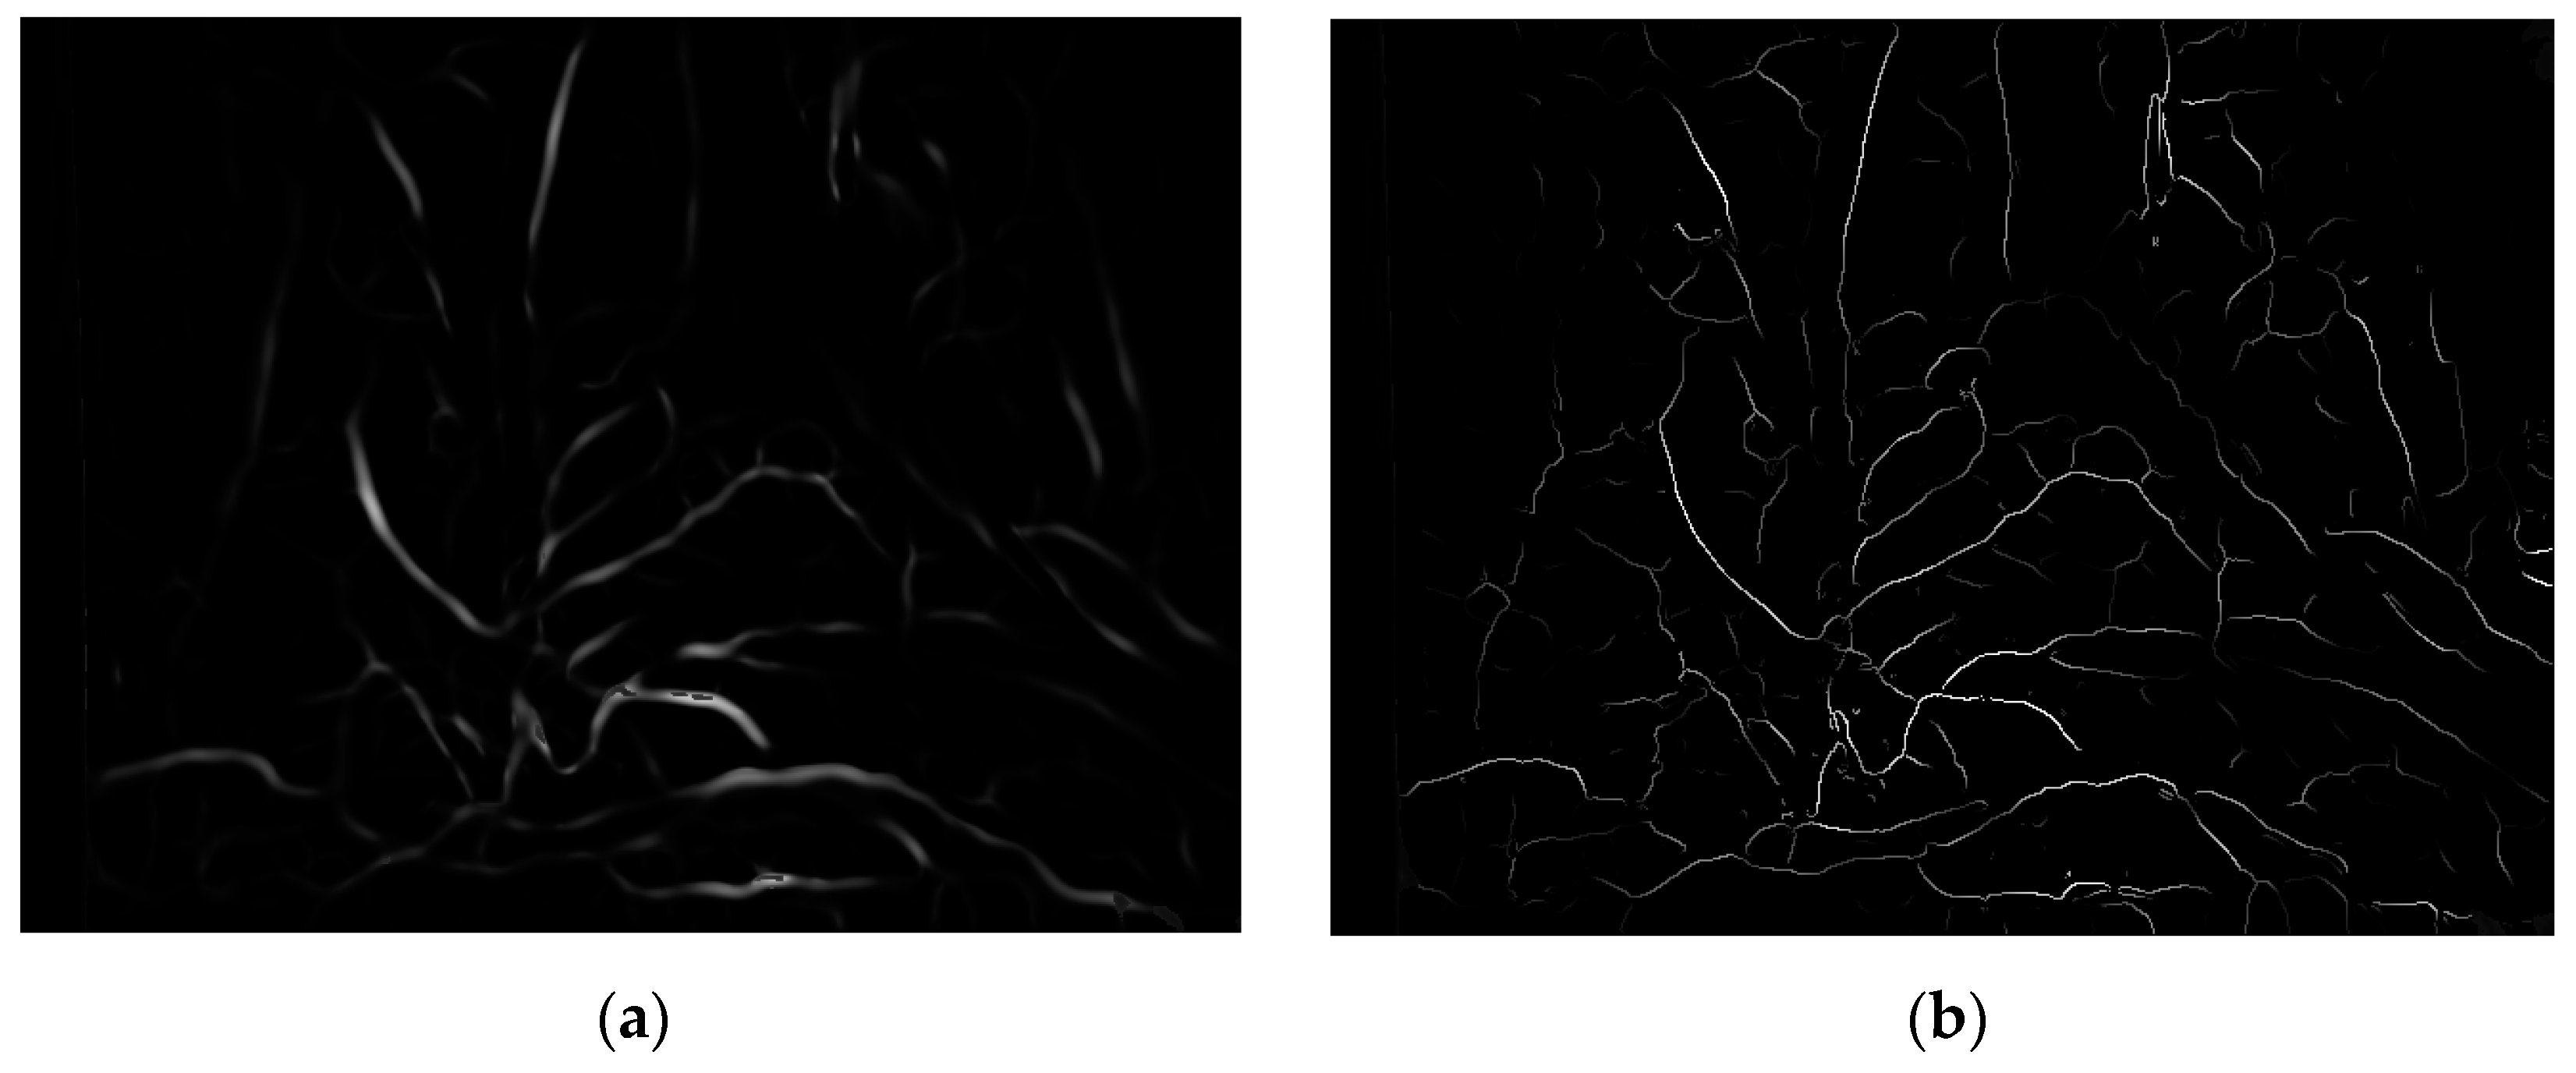

where Iridge represents ridge degree. As shown in Figure 6, (a) is the enhancement result of the Frangi enhancement method, and (b) is enhancement result of this paper method. The blood vessels after single-pixel transformation are thinner and have clearer branches compared to the original method blood vessel images in the human lumen.

Figure 6.

Enhancement results of vascular structure enhancement: (a) the Frangi enhancement method; (b) the method proposed in this paper.